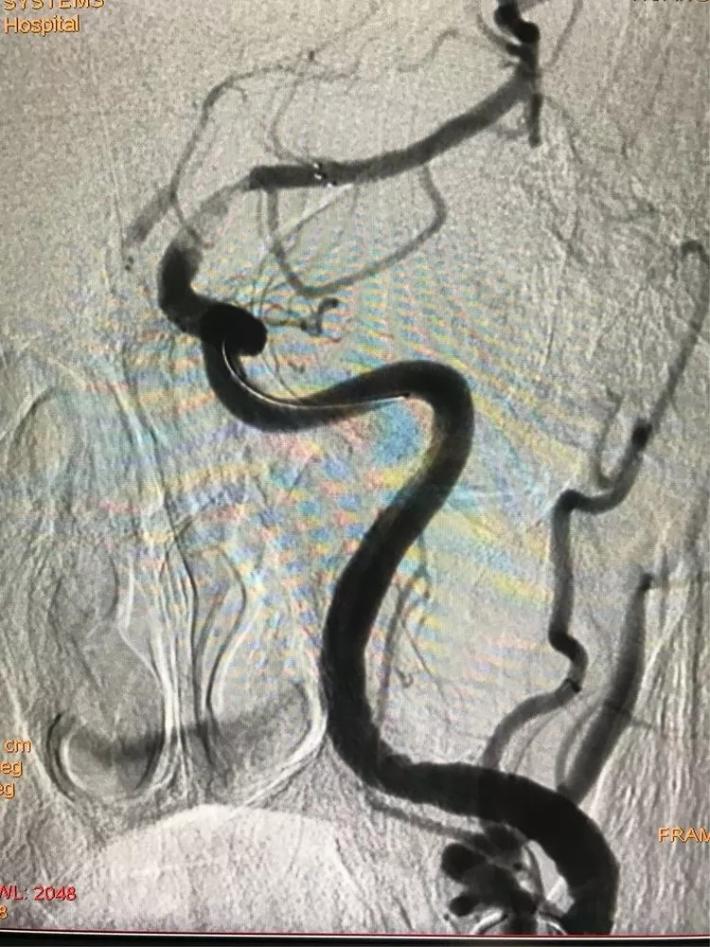

桥接动脉取栓,造影显示:基底动脉闭塞。

微导管进入基底动脉尖部,显示进入真腔。

置入支架,见基底动脉有血流。

取出支架,血管闭塞。

第二次上微导管进入真腔。

置入支架,基底动脉有血流。

取出支架,血管未开通。

第三次上微导管。

支架打开取栓。

见基底动脉血流恢复,左侧大脑后动脉血流欠佳。